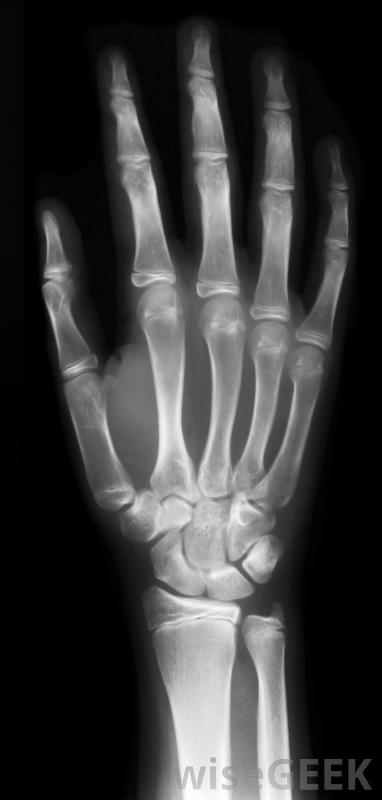

緊急護理是指為患有需要醫療護理的病人提供的醫療保健,最好在24小時內。與緊急護理不同,緊急護理必須立即提供,以防止永久性殘疾或死亡,緊急護理涉及可能導致并發癥的疾病,但不會危及生命。此類醫療護理的一個例子是為喉嚨痛的患者提供幫助。X光可以在緊急護理機構進行通常情況下,這種類型的護理是在獨立于醫院的診所中提供的,其理念是,當門診患者無法預約常規醫生,且病情不嚴重,不值得進行緊急護理時,他們可以前往緊急護理機構去急診室。緊急護理醫生充當普通醫生的替身,而該機構通過處理非急診病例來減輕急診室的負擔緊急護理設施可以通過接收無生命危險疾病的患者來減輕急診室的負擔,這些類型的護理設施在20世紀70年代開始激增許多健康保險公司強烈鼓勵他們的客戶盡可能使用緊急護理,因為這樣可以降低成本,并確保在達到緊急醫療級別之前就得到治療。例如,在24小時內治療喉嚨痛是非常容易控制的,但如果忽視它,它可能會成為一個緊急醫療事件。通過提供這種級別的醫療服務,醫生可以迅速干預。一些醫療機構接受不定期訪問,雖然在醫療機構人滿為患的時候可能會有短暫的等待。其他人要求人們預約,但他們保證在24小時內預約。任何試圖在24小時內預約醫生的人都知道,能在一天內就診會帶來很大的不同。根據醫療機構的水平,這些診所可能會提供各種各樣的服務。在需要的時候,如果情況比原先想象的更嚴重,該設施可以將患者轉診到醫院進行緊急護理。該設施還可以在實驗室進行基本的醫學測試,還可以包括一些醫療成像設備,如x射線和超聲波,以用于診斷病人在急癥治療后,可建議他或她到正規醫生或全科醫生進行隨訪。如果病人的病例需要特殊技能,該機構可能會提供轉介給一名專家,該專家將負責后續護理。